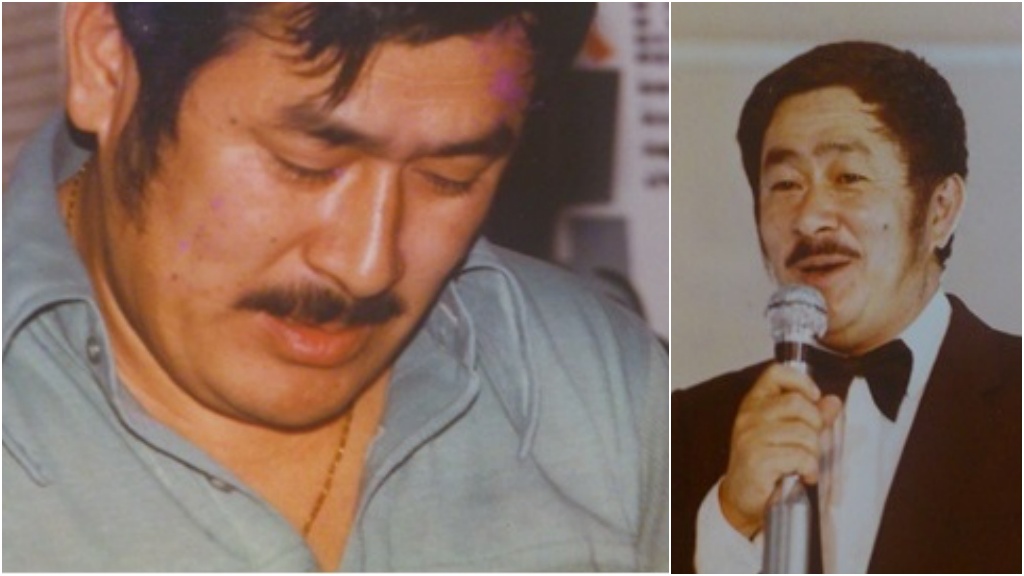

60歲原本個性幽默的男子,突然沉默寡言像變了個人,家人以為他腦中風,緊急將他送醫,檢查結果不是中風,而是腦部長腫瘤!醫師表示,膠質母細胞瘤是成人常見的腦瘤,依照腫瘤壓迫位置,可能出現頭痛、噁心想吐、個性改變等症狀。

台中一名陳姓男子原本個性風趣、能言善道,但今年7月開始,家人發現他變得沉默寡言,到9月初甚至出現說話含糊不清、右側肢體無力的症狀。此外,陳男原本身高170公分、體重65公斤,最近3個月卻掉了10公斤,到住家附近診所檢查卻查不出原因。這些異常讓家人懷疑陳男是腦中風,因此趕快送他就醫。

診斷出這顆腦瘤後,醫師透過3D立體導航精準定位,並以螢光顯微鏡精確抓準腫瘤位置,再以手術精準切除病兆,大幅降低正常腦細胞與神經手術中受損情況。術後陳先生右側手腳無力症狀解除,個性、語言能力也恢復如昔,目前正配合腫瘤團隊進行化療與放療,病況穩定。

目前治療膠質母細胞腦瘤以手術合併放射治療、化學治療為主,儘管這種腦瘤的惡性度低,但因不易根除且容易復發,屬於十分棘手的疾病,陳典廷提醒民眾出現上述症狀應立即就醫檢查,把握早期發現、治療的契機。陳男在接受手術切除腫瘤後,已恢復昔日談笑風生的性格,目前病況穩定,正持續進行化療與放療。